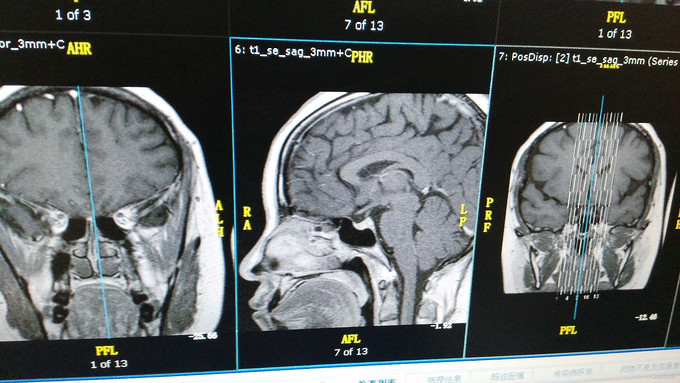

诊断:ACTH依赖性库欣综合征 治疗:转入外科手术治疗

患者于2年前出现双下肢肿胀、体重增加(2年增加约20kg,躯干增加为主)、腹胀、月经不规则、四肢乏力,1年前出现脸部色素沉着、生须,10个月前出现脸圆、双上眼睑水肿,8个月前出现左脚踝骨折,近1个月多次测血压,高峰:150/110mmHg。3套皮质醇节律结果示:失去正常皮质醇节律,ACTH、COR偏高,小剂量地塞米松抑制试验联合DDAVP试验结果示:抑制后COR:151.70>140,DDAVP:ACTH升高≥35%、COR升高≥20%。